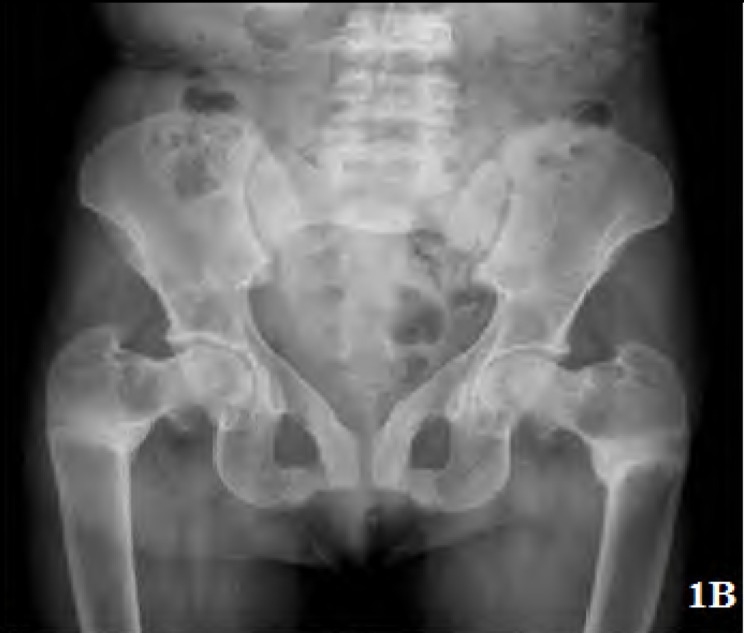

Results: Of the 380 patients with clinically suspected pSS, 25 had RTA. The median age was 32 (18-60) years. Nineteen patients had complete RTA. Six had incomplete RTA. Only 10 patients (40%) had symptoms related to RTA at presentation. Sixteen patients (64%) had present or past history of hypokalemic paralysis. Pseudofractures were seen in 7 patients and an additional 2 had subclinical radiological osteomalacia. Majority of the patients (61.2%) had a normal 25(OH) D3 level. Those with osteomalacia had significantly lower serum phosphate, blood ph and higher alkaline phosphatase. Serum calcium and 25(OH) D3 levels were not significantly different between patients with osteomalacia and those without.